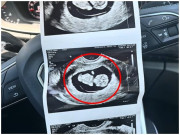

Năm 2018, khi mới 29 tuổi, Lý Tuyết Kha khiến dư luận Trung Quốc xôn xao khi quyết định chi 500.000 nhân dân tệ (hơn 1,8 tỷ đồng) để mua tinh trùng từ ngân hàng tinh trùng Anh và sang Thái Lan làm IVF. Lần đầu tiên thất bại, nhưng lần thứ hai, cô mạnh dạn chuyển ba phôi và điều kỳ diệu đã đến: cả ba phôi đều phát triển khỏe mạnh.

Giờ đây, khi ba đứa trẻ lai - hai trai, một gái đã vào mẫu giáo, Lý Tuyết Kha tiếp tục chuẩn bị cho lần IVF thứ hai tại Thái Lan. Cô cho biết đã hoàn tất kiểm tra sức khỏe và lên kế hoạch cấy phôi trong vài tháng tới. Người đẹp tiết lộ, các con lớn muốn có thêm em, đây là một trong những lý do lớn thôi thúc cô tiếp tục hành trình.